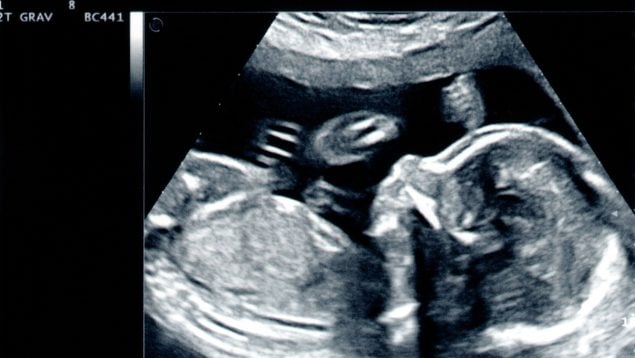

Un ensayo clínico de fase 1 realizado por investigadores de UC Davis Health y publicado en The Lancet ha demostrado que combinar la terapia con células madre con la cirugía fetal estándar es un enfoque seguro y prometedor para tratar la mielomeningocele, una forma grave de espina bífida. Por primera vez, se han implantado células madre vivas en la médula espinal dañada de fetos, con el objetivo de mejorar los resultados de salud frente a la cirugía tradicional, que aunque cierra la abertura espinal durante el embarazo, no siempre evita secuelas neurológicas como parálisis, dificultades para caminar o problemas de control vesical e intestinal.

En el ensayo, seis mujeres embarazadas con fetos diagnosticados con espina bífida se sometieron a cirugía fetal estándar más un paso adicional donde los cirujanos aplicaron células de la placenta, llamadas células madre mesenquimales derivadas de la placenta (PMSC), directamente sobre la médula espinal expuesta durante la cirugía. Estas células son conocidas por su capacidad para reducir la inflamación, promover la cicatrización y proteger el tejido nervioso.

Los seis bebés, nacidos entre julio de 2021 y diciembre de 2022, tenían sus reparaciones espinales intactas y no mostraron signos de infección, crecimiento anormal de tejido ni formación de tumores. Las resonancias magnéticas posnatales confirmaron que las anomalías cerebrales asociadas con la espina bífida, denominadas hernia del rombencéfalo, se revirtieron en todos los casos.